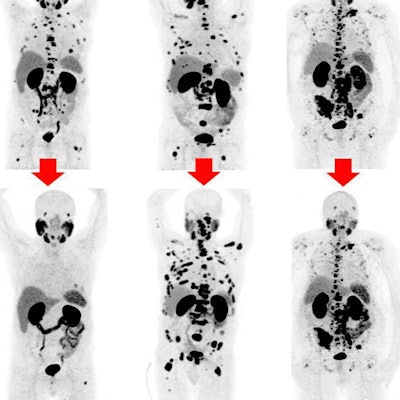

Can I see real images of chordoma in the tailbone?

Yesmany reputable sites host chordoma tailbone pictures that help patients visualize whats happening inside. Seeing the tumor can make treatment discussions feel more concrete.